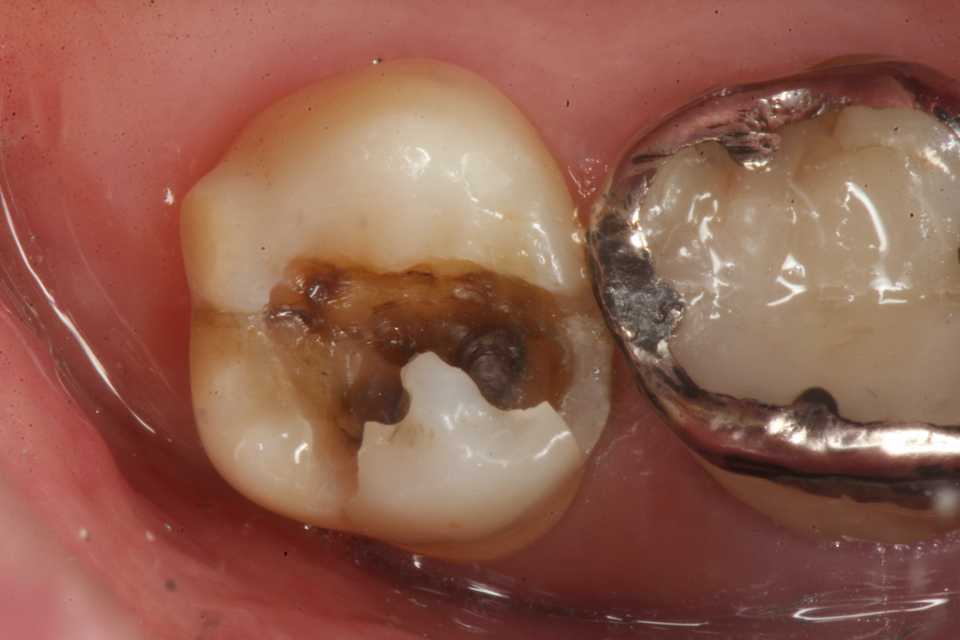

歯茎部カリエス(応力腐食割れ)0.2 2025.08.01

歯茎部カリエス(応力腐食割れ)0.1 2025.07.31

歯茎部カリエス(応力腐食割れ)0.0 2025.07.26